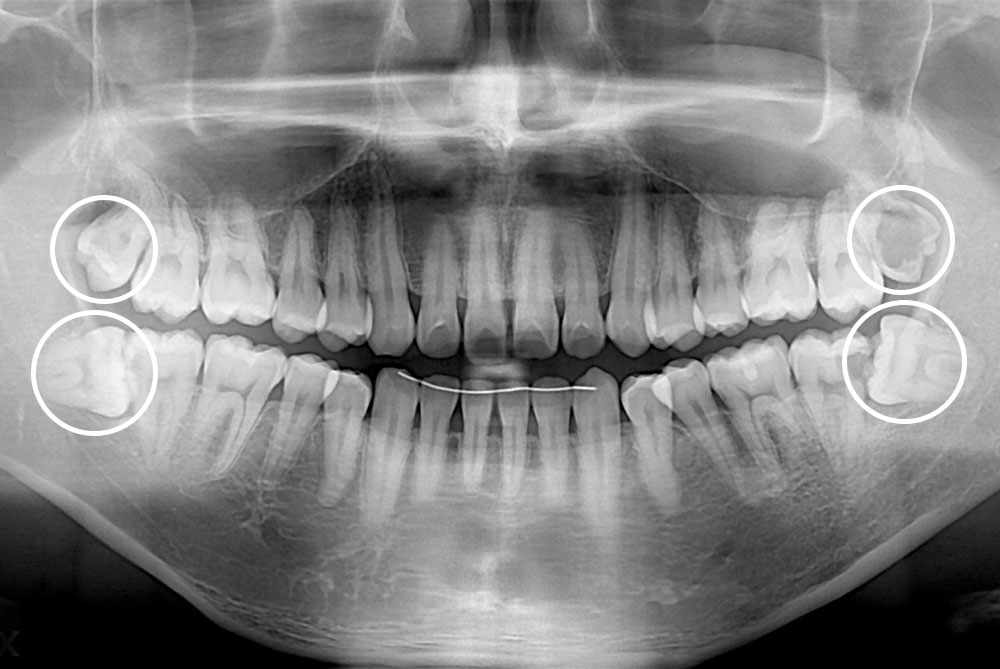

[사랑니] 매복 사랑니 발치

치료전 : 2019-09-03